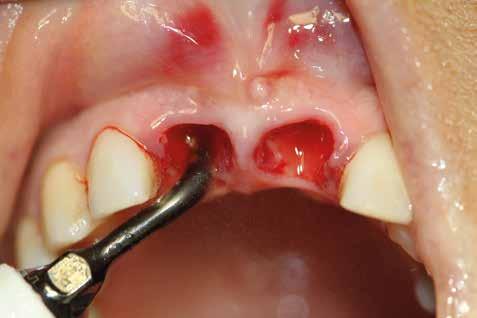

1. Accessi chirurgici (Figg. 1,2)

5.2 Accessi chirurgici

Dovendo intervenire sui tessuti molli per raggiungere l’osso sottostante, il chirurgo deve sempre scegliere il lembo più adeguato; un concetto fondamentale è che esso:

ƒ Abbia la dimensione idonea per permettere un’adeguata visuale del sito di intervento.

ƒ Sia il più integro possibile, ossia non presenti incisioni frastagliate, compressioni o danneggiamenti derivanti dalla fase di scollamento.

ƒ Sia disegnato nel rispetto della sede anatomica. È necessario porre estrema attenzione ai tessuti gengivali prossimi ai denti attigui al sito chirurgico, nonché alle strutture nobili circostanti.

Le incisioni di scarico devono essere progettate nel rispetto della vascolarizzazione dei tessuti, cosa che permette di avere una rivascolarizzazione più rapida della zona operata e, di conseguenza, una minor sofferenza dei tessuti in neoformazione. Se i tessuti periferici alla zona di intervento sono meno compromessi (poco ipossici e non frastagliati), è più semplice garantire un sigillo della ferita corretto.

In ultimo, ha grande importanza anche il momento della sutura, la scelta dell’ago, del filo e la tecnica di legatura dei nodi (fatti alla giusta distanza gli uni dagli altri e con la giusta tensione); la riuscita dell’intervento dipende anche dalla qualità con cui vengono riavvicinati i lembi in modo da non ischemizzarne o danneggiarne i bordi. (Figg. 9-14)

Esempio chirurgico di accesso tra 2 elementi dentari con conformazione della cresta alveolare ampia. Incisione del lembo in cre sta senza scarichi laterali con sollevamento di 2 lembi, palatale e vestibolare; si può notare come quest’ultimo non si estenda oltre

Una incisione lineare netta si estende coinvolgendo minimamente il dente mesiale e maggiormente in direzione distale, consente di evitare l’esecuzione di incisioni di scarico che provocano una interruzione della vascolarizzazione maggiore, senza ridurre la visibilità del campo operatorio.